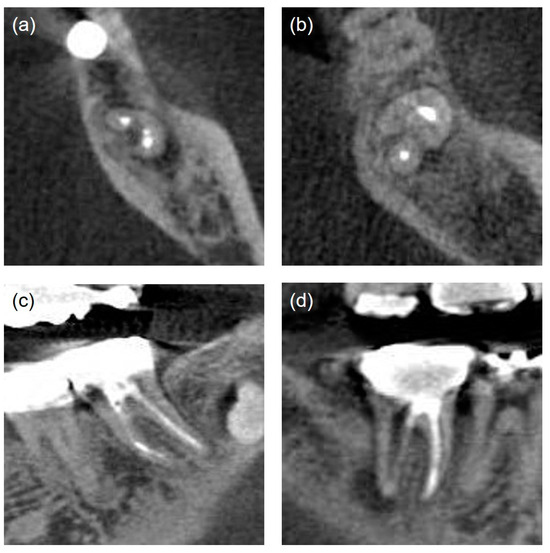

| Poor | Non-uniform radiodensity, with the canal space visible laterally and apically. Isthmus area that had not been treated (Figure 3a) | |

| Missed canals [18] | Unfilled canals appearing from cemento-enamel junction to apex including canals splitting from a main canal at coronal, mid, or apical third (Figure 3b) | |

| Iatrogenic problems | File separation. Perforation (present/absent) (Figure 3c,d) | |